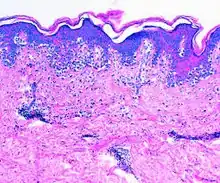

El diagnóstico se puede hacer analizando el aspecto distintivo de piel amarilla y gruesa en la zona del cuerpo afectada. La elastosis solar también puede diagnosticarse mediante una biopsia de la piel. Esto daría como resultado la baja de la eosina que mancha en las capas superiores de la piel, lo que da por resultado una mancha de óxido. Si algunas de estas lesiones no se detectan a tiempo, pueden llegar a convertirse en cáncer de piel, que es un tipo de cáncer que sí puede curarse si se da tratamiento oportuno, por lo que se recomienda una revisión anual, a fin de reducir el riesgo.[3]